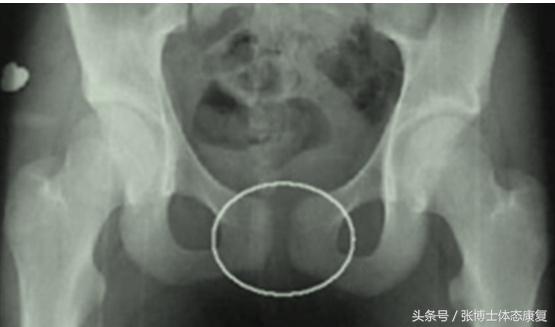

耻骨联合分离症的诊断

3、影像学检查:正常人耻骨间隙为4~6mm,孕期可增宽2~3mm。影像学X线片见耻骨联合间距离明显增宽,一般认为耻骨联合间隙超过10mm可确诊